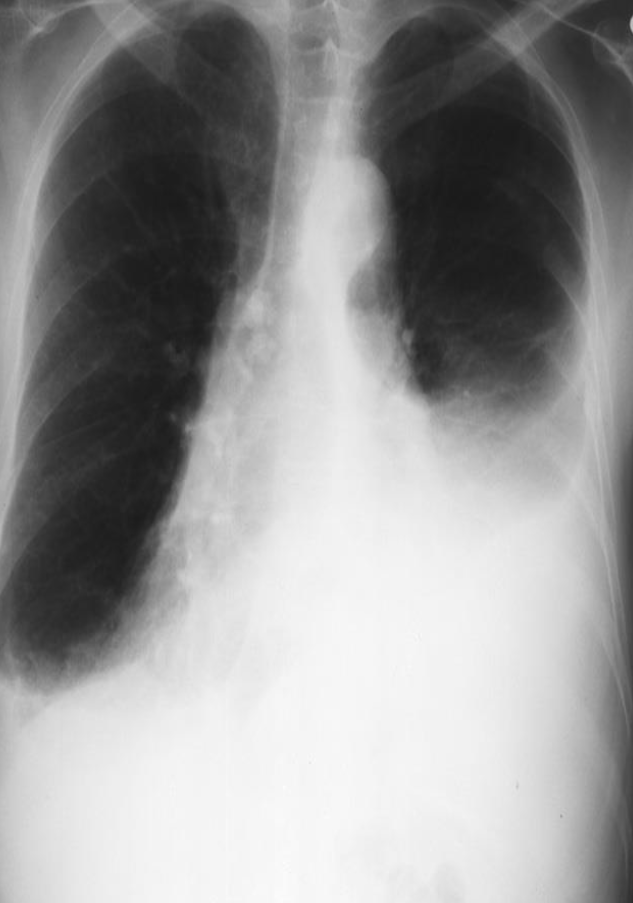

RESPIRATORY AND CARDIOVASCULAR RADIOPLOGY

A. What is the most likely diagnosis in the given images; RT lower lobe pneumonia

B. Which lobe of the lung affected by this disease in the given image. Lower lobe, reverse change of opacity from spine

A. What is the most likely diagnosis in the given images

pneumonia ex… due fever cough and the imaging

B. Which lobe of the lung affected by this disease in the given image. Right middle Lobe Lesion, due obliteration of diaphragm - and lateral of horizontal fissure opaque

Pneumonia most common due to no deviations of midline - could be truama, ectopy, etc… so follow through with case given for diagnosis

- The left hemithorax is opaque

- There is no shift of the heart or trachea

- The opacified hemithorax contains air bronchogram

- No loss of lung volume

Female patient presents with chest pain and fever

- Modality ? Plain X-ray

- Findings ? Ipsilateral shifting of trachea and heart to the abnormal side - hemithorax

- Diagnosis? Pneumonia Collapse